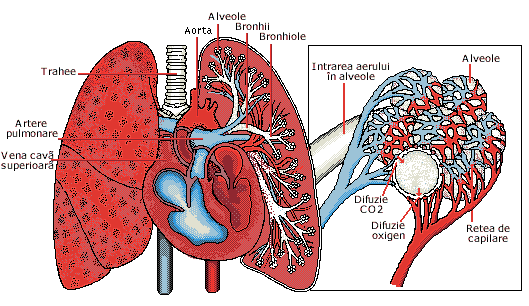

APARATUL RESPIRATOR

APARATUL RESPIRATOR Omul traieste intr-o sfera de aer, indispensabila vietii. Aparatul respirator mijloceste contactul omului cu aerul si este alcatuit din doi plamani si din condCiteste tot ... 553 cuvinte

Dimensiune mica

- fara poza |